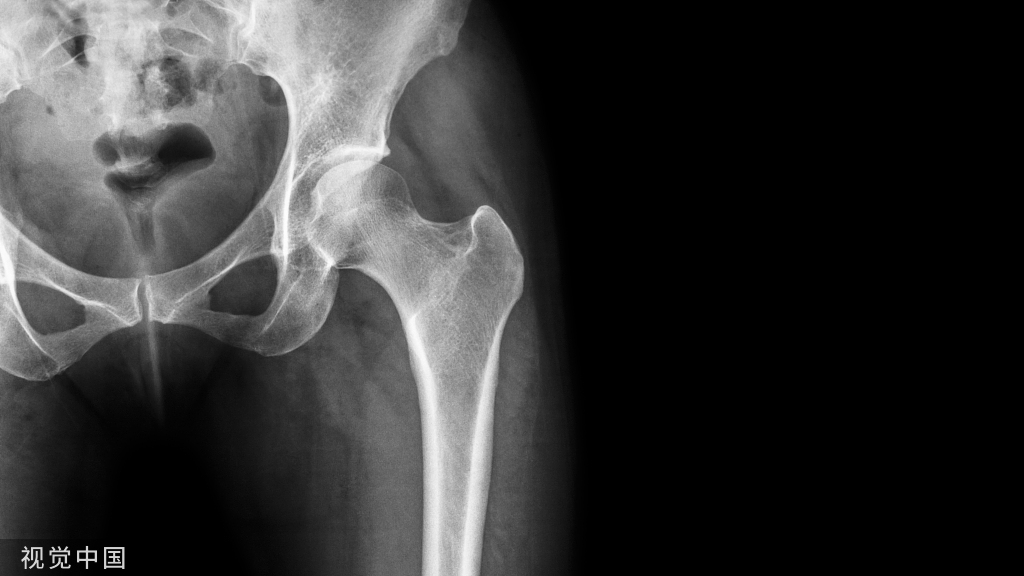

临床中我们也遇到越来越多的骨质疏松症患者,特别是骨质疏松性骨折的患者,今天就让我们通过文献来了解一下骨质疏松症的药物治疗。

在过去的几十年,骨质疏松症已经逐渐成为一个主要的公共卫生问题,无论女性还是男性,随着年龄的增长,骨骼质量逐渐变差,骨折率迅速增加,临床中我们也遇到越来越多的骨质疏松症患者,特别是骨质疏松性骨折的患者,今天就让我们通过文献来了解一下骨质疏松症的药物治疗。